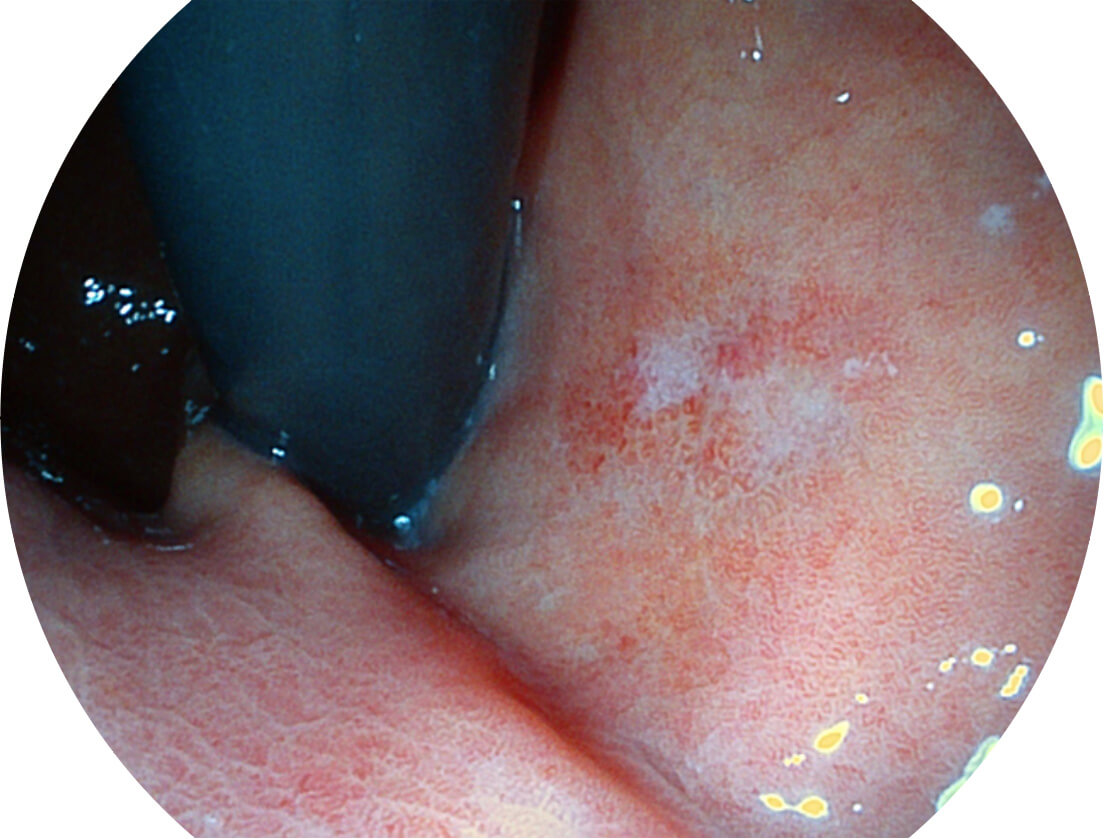

聚谱成像技术

Spectral Focused lmaging, SFI

图像具有高亮度、高黏膜血管颜色对比度的特点,且不改变粘液、食物残渣、粪便的基本颜色,可在中远景下进行观察,助力消化道早期疾病的诊断。

• 白光图像 SFI图像